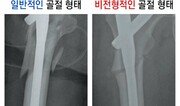

골다공증(뼈엉성증)은 뼈의 강도가 약해져 살짝 넘어지거나 부딪히는 것만으로도 쉽게 골절(뼈 부러짐)이 되는 상태를 말한다. 자칫 생명이 위험할 정도로 심각한 골절로 이어질 수 있어 주의해야 한다. 50세 이상의 성인이 가볍게 넘어졌는데 뼈가 부러지는 것은 대개 골다공증의 신호다. 특히 손목, 척추, 고관절이 부러진다면 2년 이내에 다시 골절될 위험이 매우 높다. 전 세계적으로 여성은 두 명 중 한 명꼴로, 50세 이상 남성은 다섯 명 중 한 명이 생애 동안 골다공증 관련 골절을 경험한다. 골다공증 질환에 사용하는 약은 뼈의 형성을 촉진하거나 뼈 흡수를 억제해 뼈의 양이 감소하는 것을 막거나 양을 증가시키는 약물이다. 하지만 이런 골다공증 약이 오히려 골절을 유발할 수도 있다. 형성된 지 오래된 뼈는 충격이나 살짝 금이 간 미세골절이 생길 수 있다. 정상적인 사람이라면 골 흡수가 이뤄지고 손상된 뼈는 새로운 뼈로 대체된다. 그러나 골 흡수를 억제해 뼈의 양이 줄어드는 것을 막아주는 비스포스포네이트 계열의 약물을 오래 복용한 사람은 손상된 뼈가 그대로 남아 쉽게 부러지는 비전형적 대퇴골절이 발생할 수 있다. 오래된 뼈다 보니 말랑하지 않고 푸석한 분필처럼 ‘똑’ 하고 쉽게 부러진다. 일반적인 골절 형태처럼 날카롭지 않고 뭉뚝하게 튀어나오면서 금이 가 있는 형태를 보이기 때문에 비전형적인 골절이라고 한다. 걸을 때 허벅지 바깥쪽에서 통증이 발생하고 앉아있거나 쉴 때 통증이 사라진다면 비전형적 대퇴 골절을 의심해 봐야 한다. 특히 골다공증 약을 장기 복용한 경우 통증이 발생한 부위를 주먹으로 두드릴 때 시원한 것이 아니라 심하게 아프다면 가능성이 높다. 통증은 시간이 지날수록 더욱 심해지고 절룩거림이 발생한다. 허벅지 통증은 척추 질병으로 오인되는 경우가 흔한 데 척추 질환이 원인인 경우에는 통증이 있는 부위를 두드릴 때 아픔이 별로 없고 절룩거림이 심하지는 않다. 더 정확한 진단을 하기 위해서는 X선을 찍어보면 쉽게 알 수 있다. 골다공증 약의 체내 흡수를 높이고 부작용의 위험을 감소시키기 위해서는 정해진 복용법을 지키는 것이 중요하다. 최근 보고에 따르면 비스포스포네이트 계열 약물의 복용기간은 정해진 것이 없다. 다만 복용기간이 길수록 골절이 발생할 확률은 올라간다. 김태영 건국대병원 정형외과 교수는 “비스포스포네이트 계열의 골다공증 약물은 뼈를 녹이는 파골세포를 없애서 뼈가 더 이상 녹지 않게 하는 원리”라며 “지속적으로 5년 이상 복용했다면 1, 2년 쉬었다가 다시 복용하거나 다른 약물과 함께 복용하는 방법을 고려해 볼 수 있다”고 말했다. 비전형적 골절이 발생하면 통증이 경미한 경우 약물치료를 시작한다. 약물은 뼈를 형성하는 골다공증 약제인 테리파라타이드 성분의 피하 주사 약제를 사용한다. 3개월 정도 사용하면 통증이 호전된다. 6개월 정도 지나면 통증이 사라지는 경우가 대부분이다. 하지만 처음부터 통증이 심하거나 약물치료에도 통증이 점점 심해진다면 예방적 수술을 하기도 한다. 평소 골다공증을 예방하고 골밀도 유지를 위해서는 칼슘과 칼슘의 흡수를 돕는 비타민D를 충분히 섭취하도록 한다. 지나친 육류와 나트륨 섭취는 칼슘 배출량을 증가시키기 때문에 적절히 조절해야 한다. 또 근력과 균형감각을 키워주는 운동을 규칙적으로 하면 낙상과 골절 위험을 줄일 수 있다.홍은심 기자 hongeunsim@donga.com}